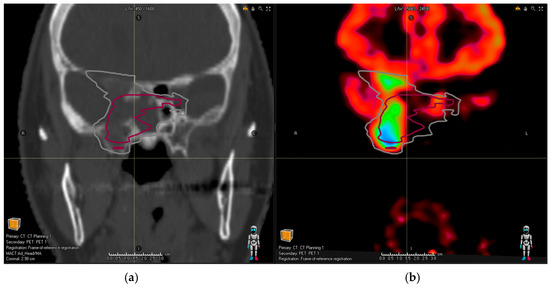

• PitNET with the bilateral involvement of cavernous sinus (as depicted in Figure 1);

Figure 1. (a) Planning the CT image of a patient with pituitary adenoma. Pink contour shows common MRI volume; after the addition of PET/CT, (b) the observers identified an infiltration in the left cavernous sinus (white contour).

In all these cases, the new tumor volume first identified with the aid of DOTA PET/CT should be considered relevant for the proton treatment plan. There was no relevant tumor volume missed by observers in MRI compared to PET/CT for glomus tumors. Figure 1a shows the planning CT image of a patient with pituitary adenoma; Figure 2a shows the planning CT image of a patient with an aggressive pituitary adenoma.